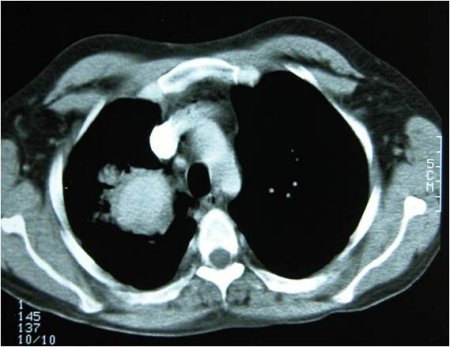

Major vessel involvement [Figure caption and citation for the preceding image starts]: Pulmonary aneurysmFrom the collection of Yusuf Yazici, MD [Citation ends].

Rare. Possibilities include thrombophlebitis, deep vein thrombosis, cerebral venous thrombosis, and aneurysm formation.

Aneurysm formation can be life-threatening, especially in the pulmonary vasculature, when haemoptysis would be the presenting symptom.[17]

Lung imaging

Haemoptysis may be the only presenting symptom of pulmonary aneurysm in Behcet's syndrome.

High-resolution chest computed tomography (CT) is recommended. CT angiography and invasive angiography are alternative studies if high-resolution chest CT does not confirm the diagnosis. High-resolution CT or CT angiography, chosen depending on the availability and local expertise, is used to screen for pulmonary aneurysm in patients with thrombophlebitis or other aneurysms (e.g., in the vena cava, hepatic veins).